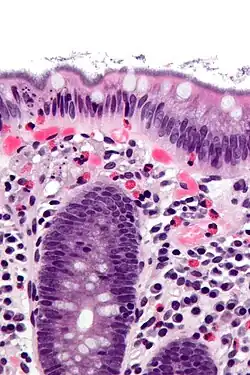

| Histopathology of intestinal spirochetosis, showing basophilic, fringe-like, end-on-end attachment of filamentous densely packed spirochetes on the surface epithelium of the intestinal mucosa.[1] H&E stain. | |

It is diagnosed by examination of tissue, i.e., biopsy. A hallmark finding is the presence of a “false brush border” on the luminal surface of the epithelium, formed by dense linear colonization of spirochetes.[4]